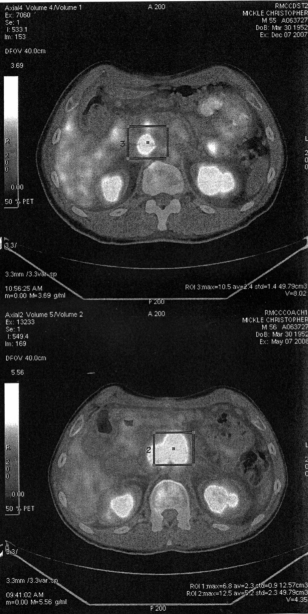

Here is a scan of two PET scans. The top is the one he had done in December. The bottom was the most recent one done this month. The little square indicates the large tumor in his abdomen. And shows how much the tumor has grown.

We got the results of the latest PET scan this afternoon and the news is not good. The latest chemo Chris went through was not successful. The lymphoma is still active and has in fact spread. We keep fighting. He will start yet another new chemo regimen asap. This time it is called Hyper CVAD. As we understand it, it will not be a walk in the park for him. He's ready to do what ever it takes. The transplant will be rescheduled for July. Since his blood transfusion on Saturday, Chris has had more energy and, until today, his spirits were high. It is hard, but we try to keep that optimism going.